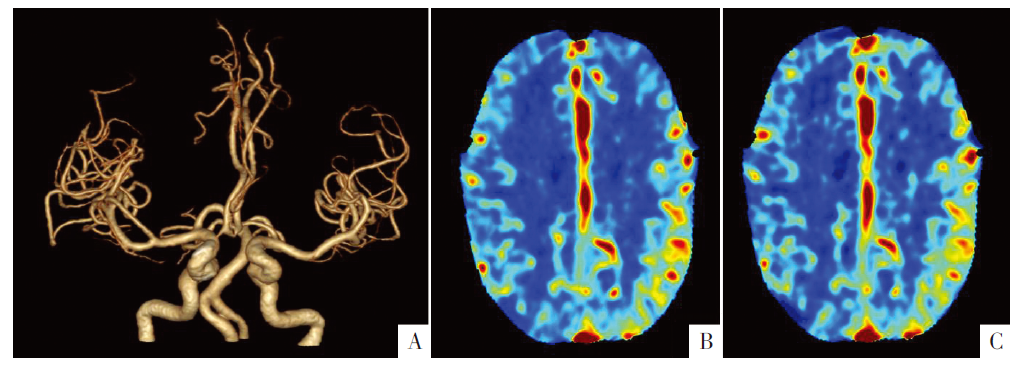

图2

头颅CTA和CTP影像。A图为CTA容积再现(VR重建)。B、C图为CTP影像,B图为脑血流量,C图为脑血容量。